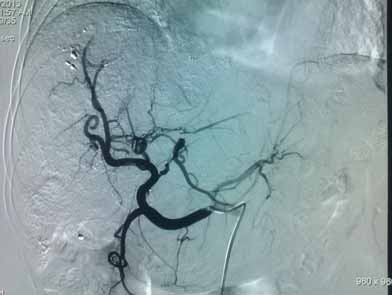

胃左动脉超选择造影见肿瘤血管增多、杂乱,示块状肿瘤染色

栓塞完成后肿瘤血管消失